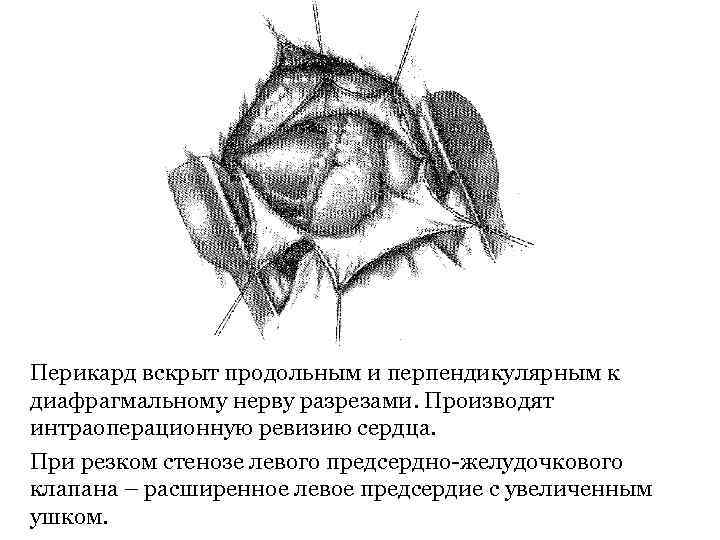

Вскрытие перикарда (перикардиотомия) • Показание. Гнойный перикардит. • Техника. Операцию производят из бокового или переднебокового доступа в 4 межреберье. Легкое отводят дорсально, перикард обычно вскрывают дорсальнее диафрагмального нерва и параллельно ему. Второй разрез перпендикулярно первому вдоль проекции предсердножелудочковой борозды – обеспечивает дренирование полости перикарда в послеоперационном периоде.

Вскрытие перикарда (перикардиотомия) • Показание. Гнойный перикардит. • Техника. Операцию производят из бокового или переднебокового доступа в 4 межреберье. Легкое отводят дорсально, перикард обычно вскрывают дорсальнее диафрагмального нерва и параллельно ему. Второй разрез перпендикулярно первому вдоль проекции предсердножелудочковой борозды – обеспечивает дренирование полости перикарда в послеоперационном периоде.

Перикард вскрыт продольным и перпендикулярным к диафрагмальному нерву разрезами. Производят интраоперационную ревизию сердца. При резком стенозе левого предсердно-желудочкового клапана – расширенное левое предсердие с увеличенным ушком.

Перикард вскрыт продольным и перпендикулярным к диафрагмальному нерву разрезами. Производят интраоперационную ревизию сердца. При резком стенозе левого предсердно-желудочкового клапана – расширенное левое предсердие с увеличенным ушком.

После опорожнения полости перикарда в рану вставляют резиновый дренаж, края раны сближают редкими швами.

После опорожнения полости перикарда в рану вставляют резиновый дренаж, края раны сближают редкими швами.